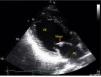

Primary cardiac tumors are rare in all age groups, with a reported prevalence of 0.001–0.03% in autopsy series. We report the case of a 37-year-old man, with no relevant medical history, who was admitted to the emergency department with sudden-onset right hemiparesis. Diagnostic studies revealed a small hypodense area in the left putamen and he was admitted to the stroke unit with a diagnosis of ischemic stroke. During investigation of the cause of stroke in such a young patient, he underwent transthoracic echocardiography, which showed a mass attached to the anterior leaflet of the mitral valve (Figure 1). Transesophageal echocardiography was then performed to clarify the picture, which confirmed a small echodense pedunculated mass, 0.5 cm2 in size, with well-defined borders, features typical of a fibroelastoma (Figures 2 and 3), attached to the atrial surface of the anterior mitral valve leaflet without causing mitral regurgitation (Figure 4). The rest of the echocardiographic examination revealed an estimated left ventricular ejection fraction of 65% and no other valvular abnormalities. The patient was subsequently referred to the cardiothoracic surgery center for surgical excision of the mass. Macroscopic examination showed a 0.6-cm whitish spiculated nodule with a soft elastic consistency. Histopathological study revealed cardiac myxoma. We present this case to highlight the unusual presentation, particularly its echocardiographic features.